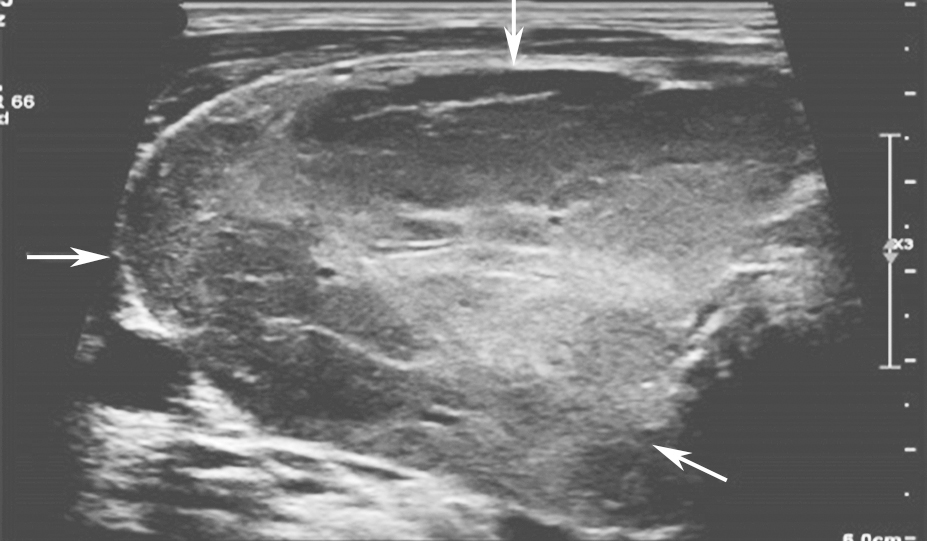

(十)甲状腺滤泡癌

甲状腺滤泡癌和滤泡腺瘤在超声上鉴别有一定困难,即使是FNA细胞学也很难鉴别。但有报道认为:与甲状腺乳头状癌不同,甲状腺滤泡癌常为等回声或高回声,微小钙化很少见,病变多伴有厚薄不一的低回声晕或者局部低回声晕。彩色多普勒血流信号丰富也是该类病变的特点之一(图11、图12)。

图11右侧颈部纵切面:甲状腺右叶中部中等回声(箭头所示):内部回声不均伴厚薄不一低回声晕

图12右侧颈部纵切面(与图3-3-11同患者、同切面):中等回声彩色多普勒血流信号丰富而杂乱